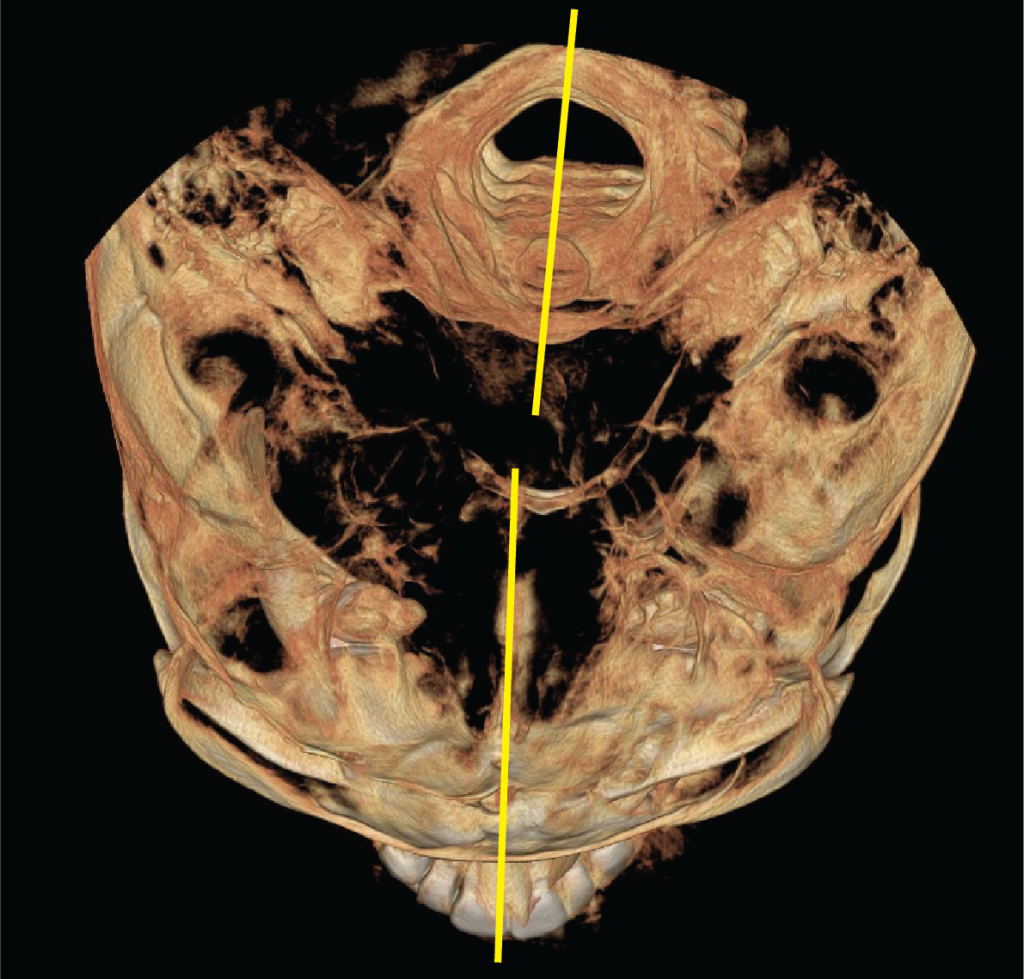

Figure 10: Spine-cranium asymmetry in NM patients. CBCT reconstruction of an axial view, demonstrates a significant asymmetry in the patient’s spinal and cranial axes.Â